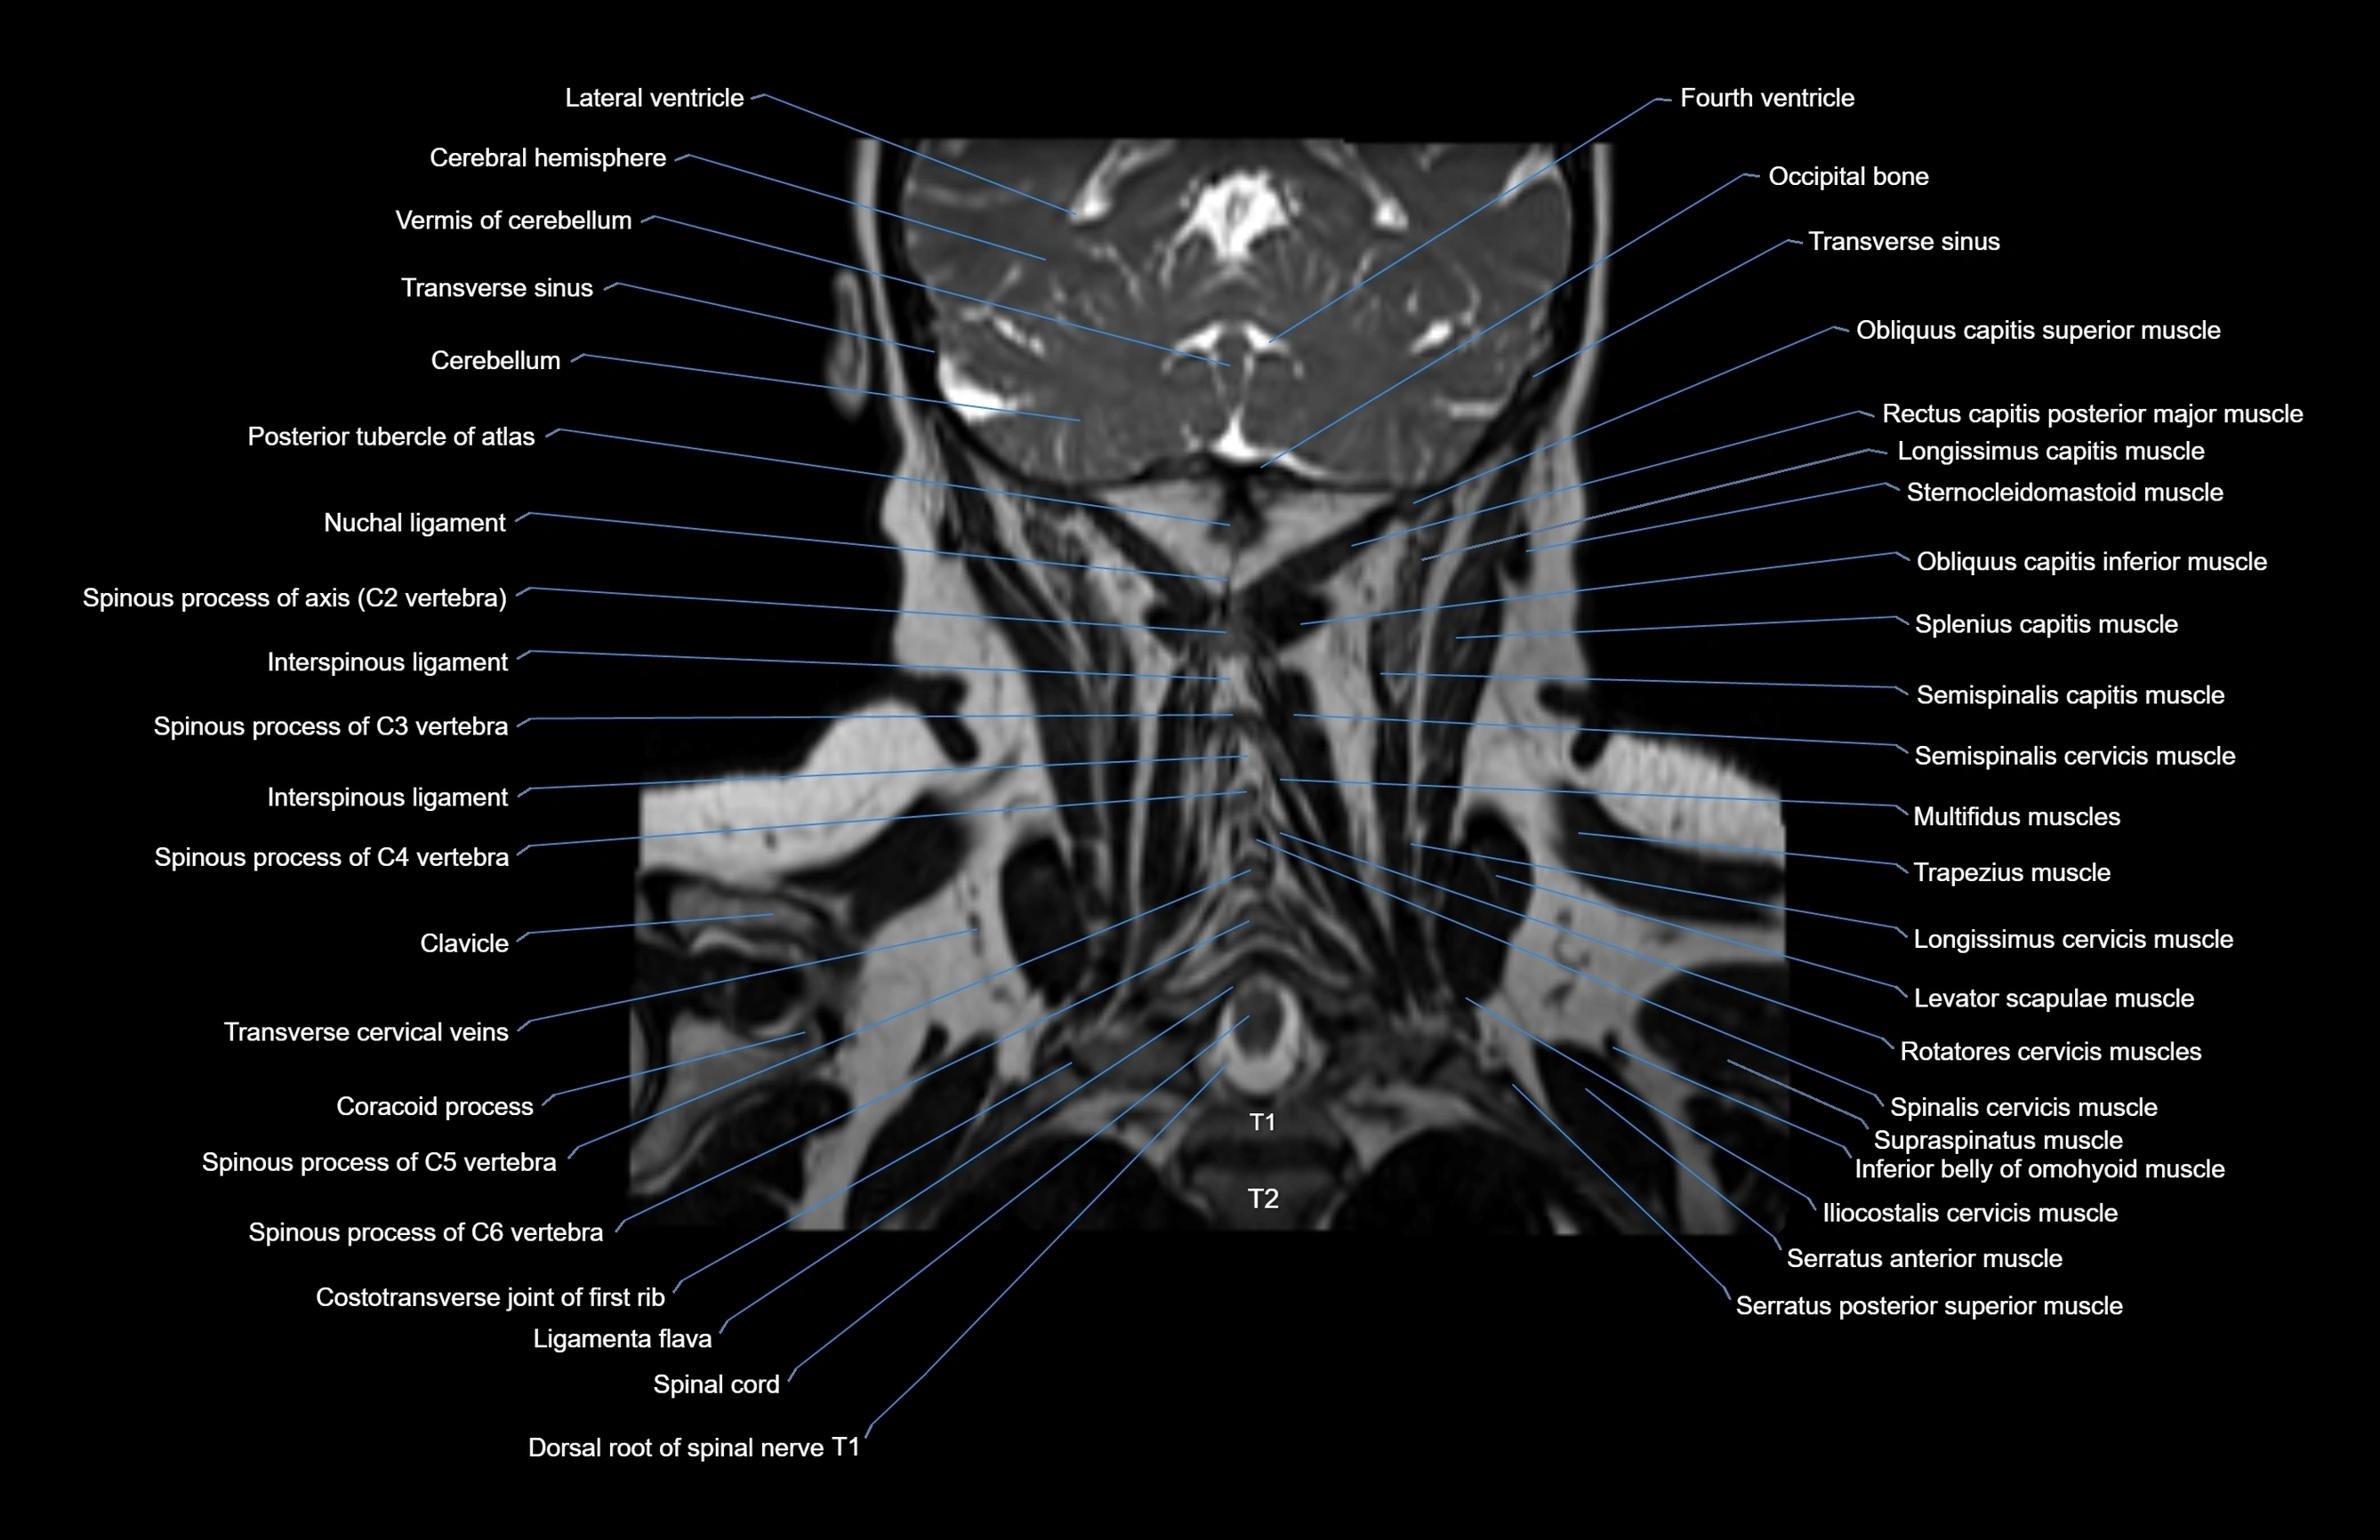

MRI images